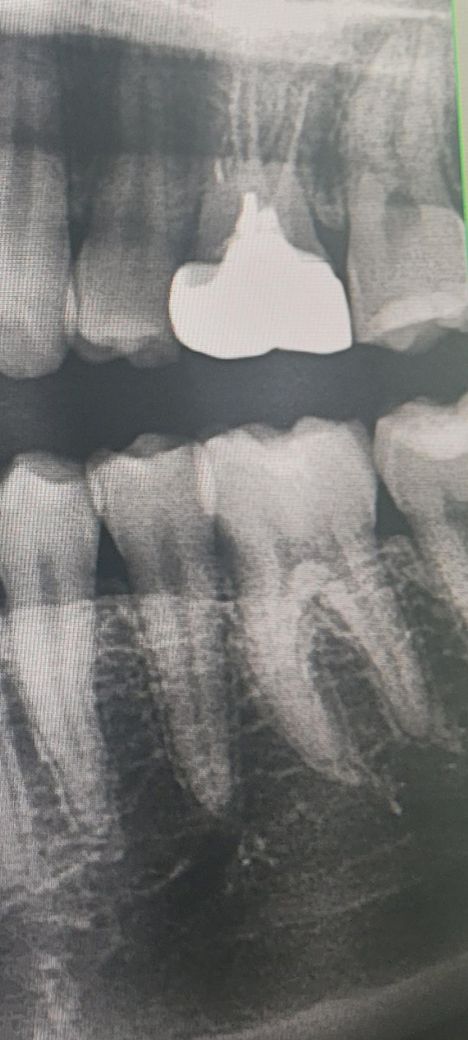

제 소구치에 문제가 있을까요?확인해주세요

대구치랑 더 가까운 소구치에 문제가 있을까요?

사진은 한달 전 사진인데요 한달만에 잇몸이나 치아가 나빠질 수도 있나요?

어제 양치하다가 저 치아에 소리도 나서요..

엑스레이 상으로는 크게 문제가 될만한건 보이진 않습니다. 크게 걱정은 안하셔도 될것같습니다.

사진상에서는 특별히 문제가 보이진 않는 것 같습니다. 통증이 있으면 치과 가보시는 게 좋겠습니다.

사진으로 봤을 경우에는 치아에 크게 문제가 없어 보입니다.

하지만 치아에 금이갔거나 했다면 사진에 보이지 않을수도 있습니다.

특별히 엑스레이상 문제가 있어보이진 않습니다 양치하다 소리가 나는 건 흔치 않은 증상이나 치아 사이에 껴있던 음식물이 빠지면서 소리가 나는 경우도 있을 것 같습니다